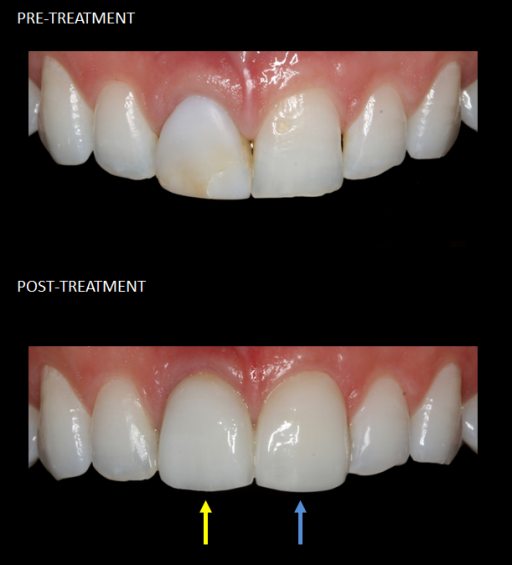

Front teeth restored with a single implant (yellow) and a matching veneer (blue).